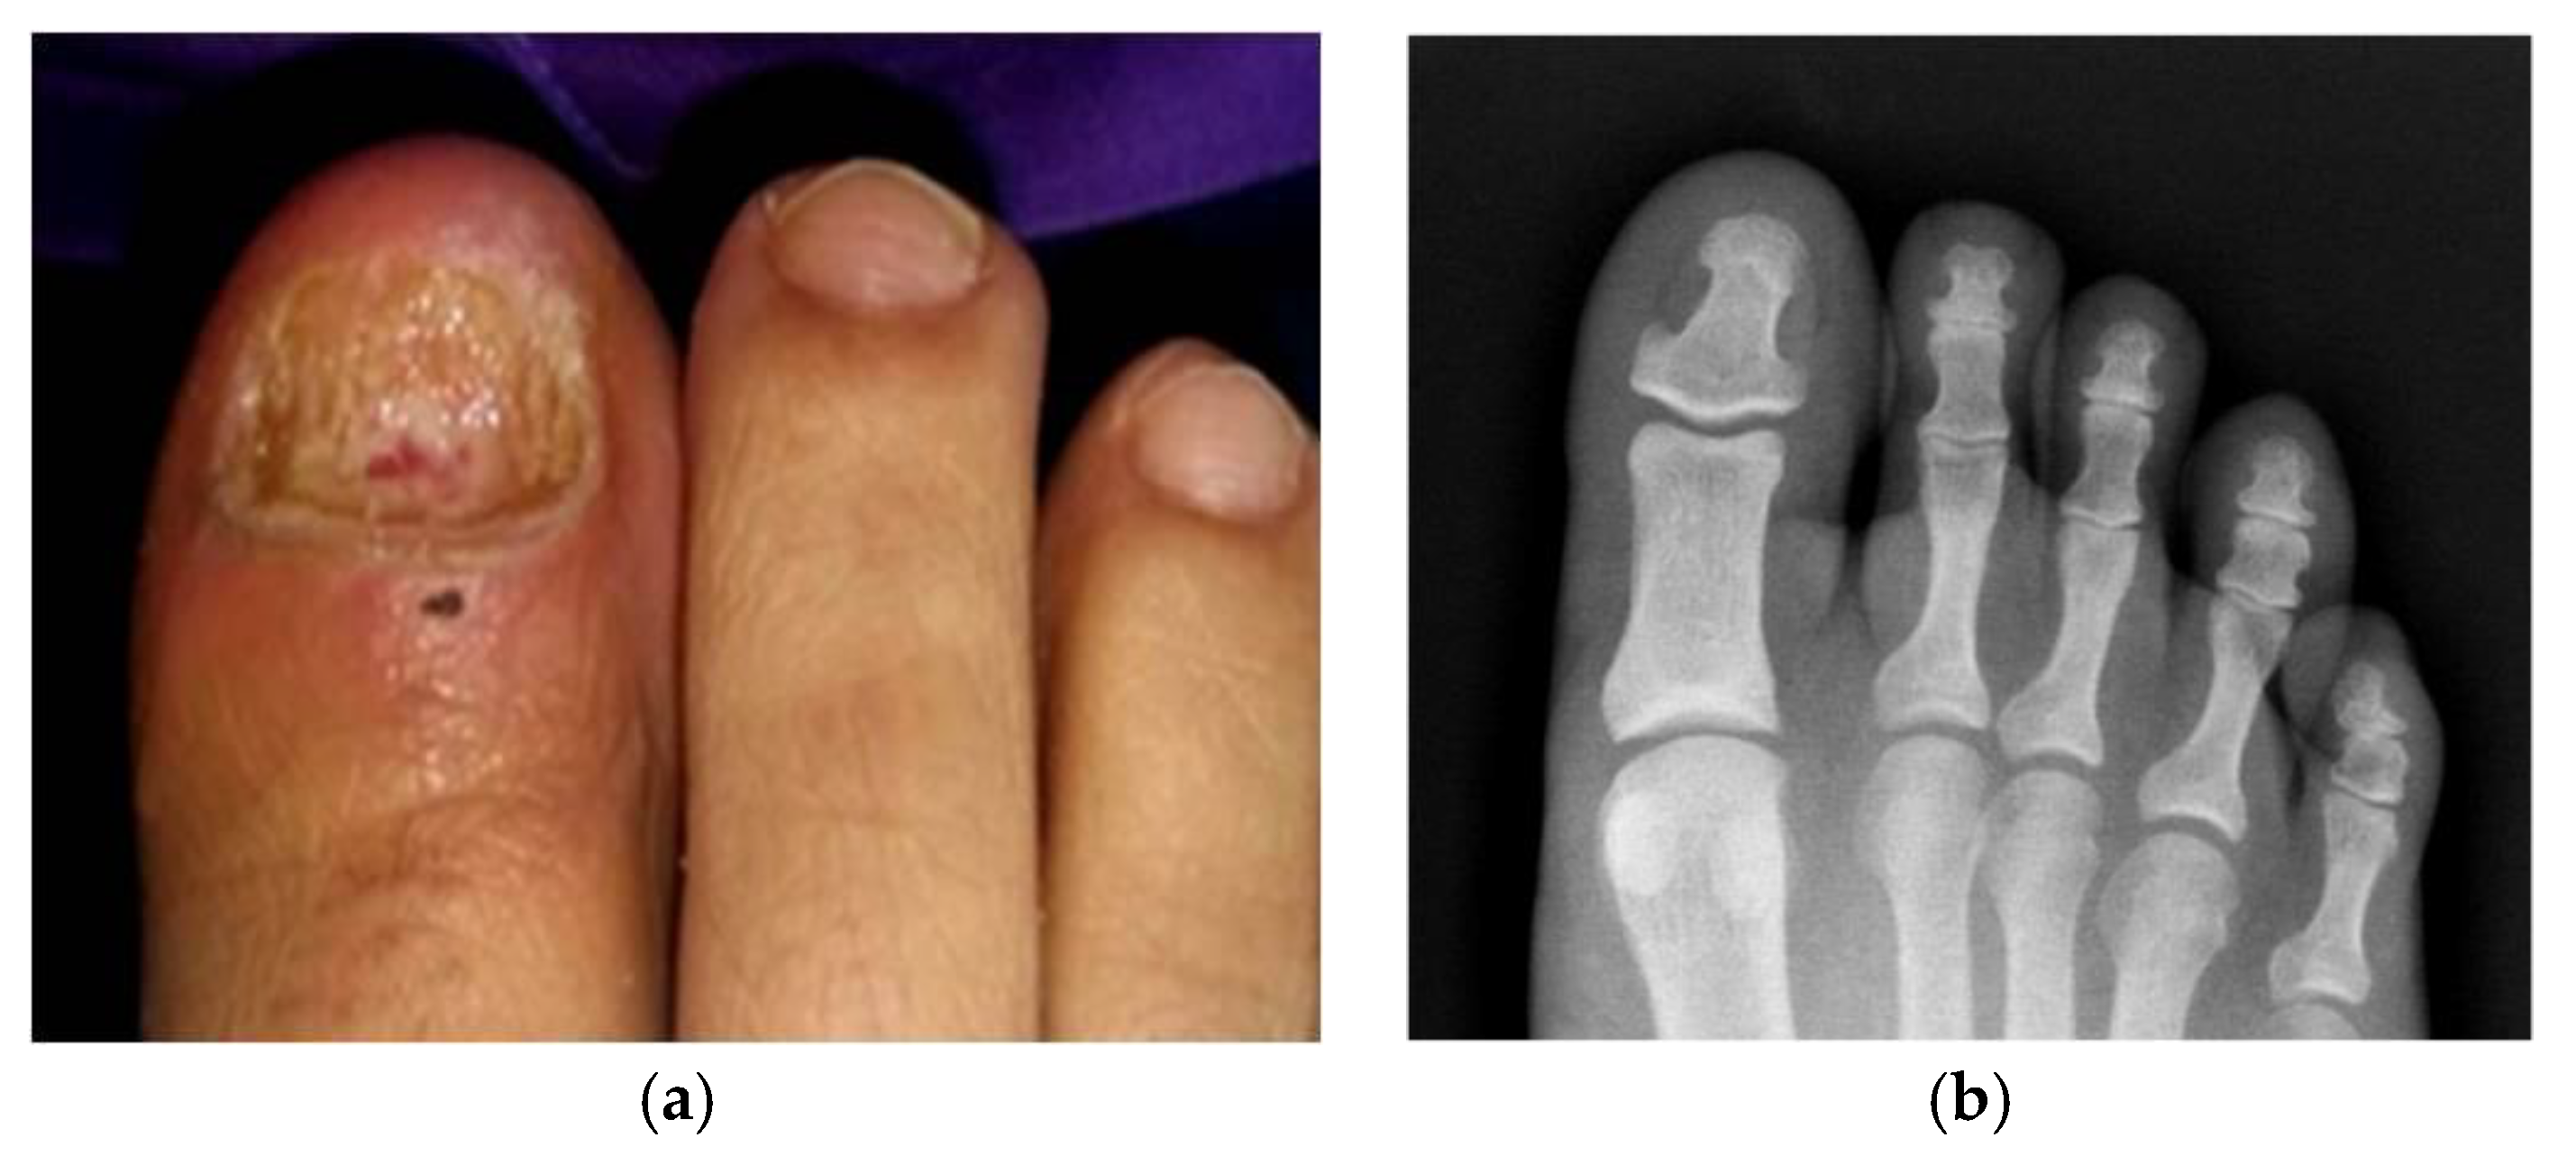

2. Case Presentation